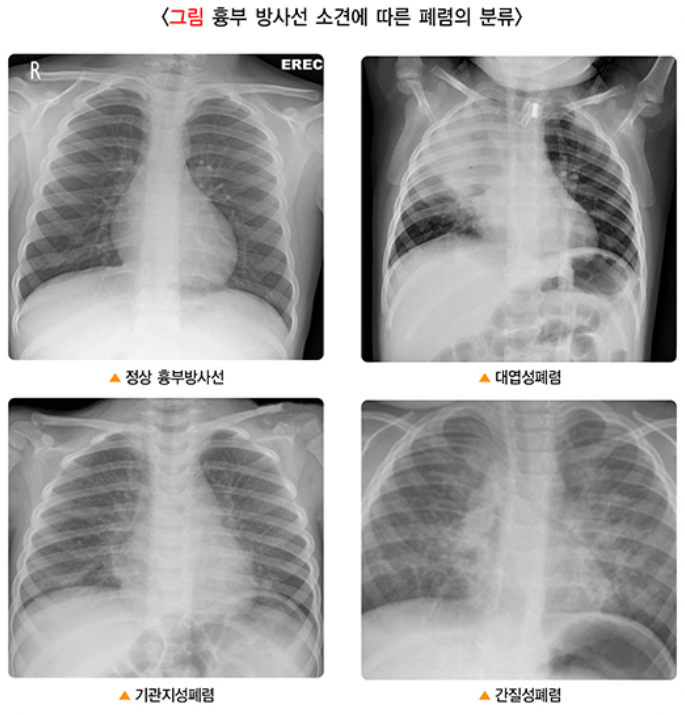

2)흉부 엑스레이: 폐렴의 범위와 위치를 확인하기 위해 흉부 엑스레이를 촬영합니다.